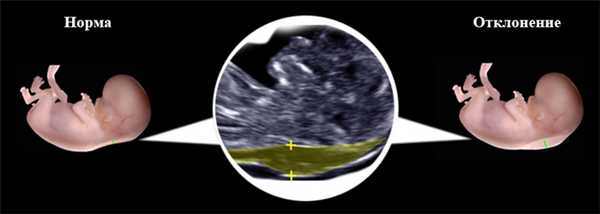

Толщина воротникового пространства (ТВП)

Воротниковое пространство - это скопление жидкости в области шеи плода. В нашей стране воротниковое пространство у плода исследуют в первом триместре беременности при скрининговом ультразвуковом обследовании в 10-14 недель беременности. Толщина воротникового пространства (ТВП) это область между внутренней поверхностью кожи плода и наружной поверхностью мягких тканей, покрывающих шейный отдел позвоночника.

Изображение воротникового пространства можно оценивать как с помощью трансабдоминального, так и трансвагинального сканирования. Оценка ТВП у плода проводится при значениях копчико-теменного размера (КТР плода) от 45 до 84 мм и позволяет заподозрить хромосомные аномалии, особенно трисомию 21-й хромосомы (синдром Дауна) и сформировать среди беременных группу риска по рождению детей с врожденной и наследственной патологией.

Толщина воротникового пространства (ТВП) на УЗИ

Толщина воротникового пространства. Норма

Толщина воротникового пространства в норме составляет от 0,7 до 2,7 мм в зависимости от срока беременности. Риск рождения ребенка с хромосомными аномалиями заметно увеличивается с утолщением воротникового пространства и возрастом матери. Поэтому всегда, когда толщина воротникового пространства составляет 3 мм или более, врач назначает проведение инвазивного кариотипирования (исследования, которое позволяет на клеточном уровне выявить возможность рождения малыша с генетическим синдромом, таким как синдром Дауна, Эдвардса, Патау и др), с использованием биопсии ворсин хориона (на анализ берется кусочек ткани плаценты) или раннего амниоцентеза (с целью получения образца амниотической жидкости).